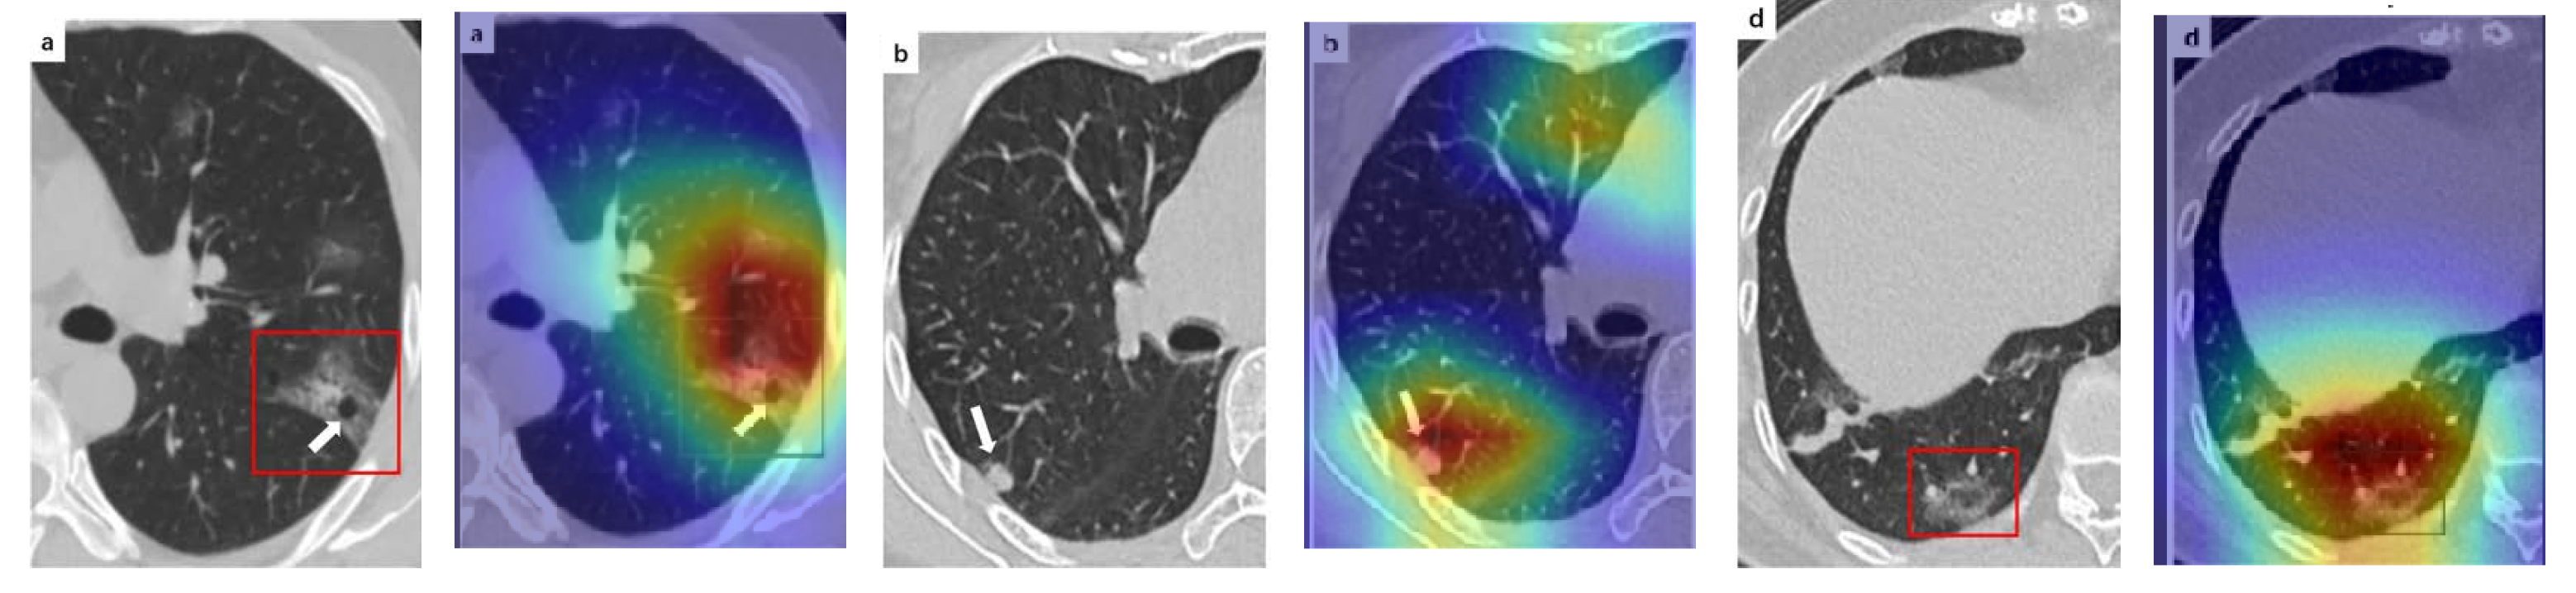

A wide variety of typical and atypical chest CT abnormalities of COVID-19 patients have been reported in various studies [61,62]. In order to investigate the ability of our models to identify COVID-19 cases outside the considered datasets and localize their CT findings, we tested our models on external CT images extracted from these two publications, as they feature typical findings of COVID-19 pneumonia marked by specialists. To make sure that none of the extracted images were unintentionally included in our datasets, specifically the COVID19-CT dataset, we used the model trained on the SARS-CoV-2 dataset. First, the InceptionV3 model was used to classify the extracted CT images. The model was able to correctly classify the given CT images as COVID-19. Second, in order to interpret the model’s generalization capabilities, we applied the Grad-CAM technique to visualize the regions of abnormalities that are considered. By assessing the different CT images in Figure 15, we can see that the model accurately localizes the disease-related regions. Even more interesting is the fact that the model ignores any specific marks in the images such as the letters and only localizes the COVID-19-related regions. These further experiments prove the success of our models to learn distinguishable visual features related to COVID-19, and to correctly classify CT images outside the datasets on which they are trained and tested.

Figure 15.

Examples of CT images taken from these two publications [61,62]. The CT images were correctly classified as COVID-19 cases, and the abnormal regions are accurately detected as in the localization maps.

In order to investigate the capacities of the different models to accurately localize identical or similar important regions, we employed the model with the lowest accuracy, i.e., SqueezeNet, which was fine-tuned on the SARS-COV-2 dataset to classify the unseen CT images taken from [61,62]. Moreover, we provide the Grad-CAM localization maps for a direct comparison. Figure 16 illustrates CT images, which represent the first two rows in Figure 15, and their corresponding localization maps. For most of the cases, both models looked exactly at similar regions representing the COVID-19 manifestations. However, for some images, SqueezeNet looked at irrelevant regions, such as the top left corner.

Figure 16.

Grad-CAM visualizations for the same CT images in the first two rows of Figure 15. The CT images were correctly identified by SqueezeNet as COVID-19 cases with relevant localization of the disease-related regions.

Although we trained our models using CT images where both lungs are visible in the scans, we tested them on some external CT scans where only one lung is visible. The CT scans were extracted from the paper [61] and show different CT manifestations of COVID-19 marked by red squares or white arrows. Our models were able to classify them correctly as COVID-19 cases. Intriguingly, when applying Grad-CAM we can see from Figure 17 that all regions of abnormalities are accurately localized. This also proves the potential of our models to detect COVID-19 abnormalities in CT images outside the dataset used for training.

Figure 17.

Example of annotated CT scans with different manifestations of COVID-19 taken from [61], and their corresponding localization maps. Our models were able to identify them as COVID-19 cases and accurately localize their COVID-19-associated regions.